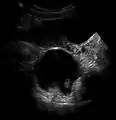

A complex cyst due to a dermoid as seen on ultrasound